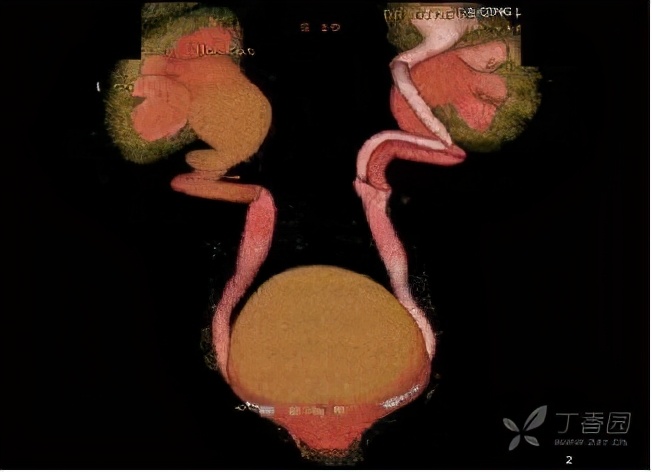

在增强CT检查的时候,得到了如下检查图像

检查图像显示,该病人的双侧输尿管于膀胱开口处过低,还伴有左侧部分双肾盂、输尿管畸形,这些图像给我们的印象是:是不是存在异位开口的可能?